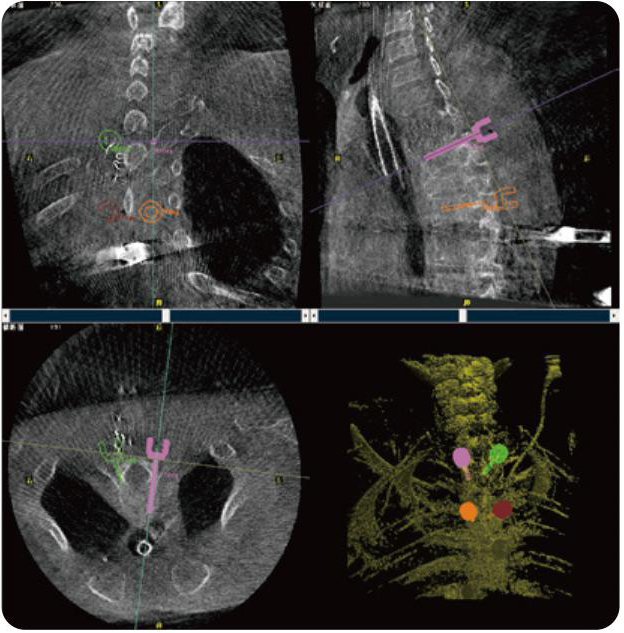

PL300B可應用于多節(jié)段脊柱外科手術,輔助醫(yī)生定位病灶部位,為脊柱外科手術(經(jīng)皮椎體成形術、椎弓根螺釘內固定術等術式)提供術前手術流程規(guī)劃、入釘位置、角度可視化引導,模擬仿真入釘輔助。

PL300B搭配普愛醫(yī)療自主研發(fā)生產(chǎn)的平板3D C形臂,借助一體化自適應配準( 軌跡配準)技術,通過追蹤C形臂三維采集軌跡,自動完成圖像坐標建立和系統(tǒng)坐標配準。配準精度更高,操作步驟少,系統(tǒng)運作效率高。